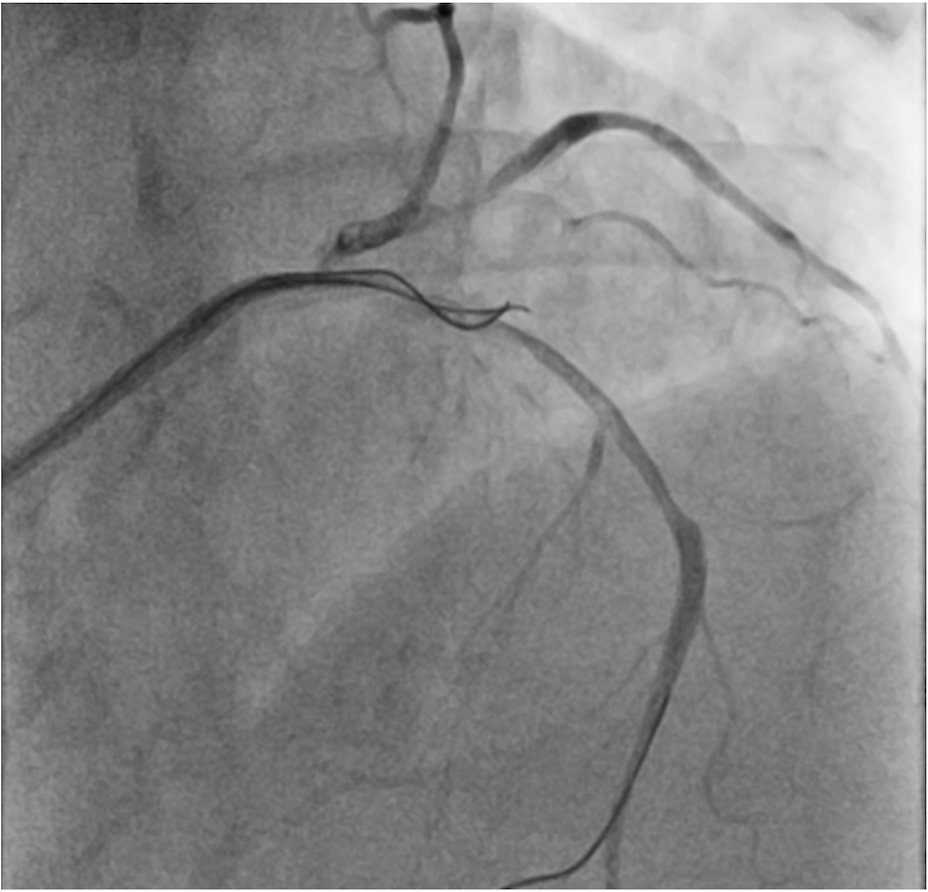

A 75-year-old man was admitted for non-ST-segment elevation myocardial infarction (NSTEMI). Coronary angiography showed focal severe disease at obtuse marginal artery (OM) and severe medina 1,1,1 bifurcation disease involving proximal to middle left anterior descending artery (LAD) and a sizable diagonal branch (Figure 1A, Video 1). With a 6-French extra backup (EBU) 3.5 guide catheter, the LAD was wired with a workhorse guidewire. The diagonal branch had a retroflex takeoff and initial wiring was subintimal (Figure 1B). Parallel wire technique (PWT) with Gaia Next 1 (Asahi Intecc) successfully rewired the true lumen and steered into the distal part of the diagonal branch (Figure 1C, D; Video 2). The LAD was provisionally stented with the diagonal branch protected by jailed balloon technique (JBT) of a 2.0 mm semi-compliant balloon, followed by stenting of the OM (Figure 1E). The final angiographic results were good (Figure 1F, Video 3).